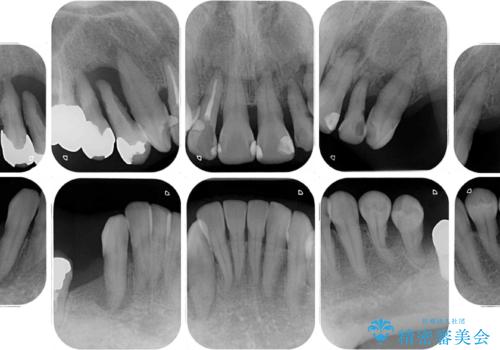

- 歯周病を放置したことで奥歯が抜け、前歯も痛くなってきたとのことで来院された患者様です。

奥歯はほとんどを抜歯しなければならない状態であり、抜歯をせずに済む歯も歯周外科処置や矯正治療を行う必要がある状態でした。

歯を抜かないといけない部分はインプラントとオールセラミッククラウンにより咬合を回復させ、歯周外科処置を行う歯については、同じくオールセラミッククラウンにて補綴治療を行うこととしました。